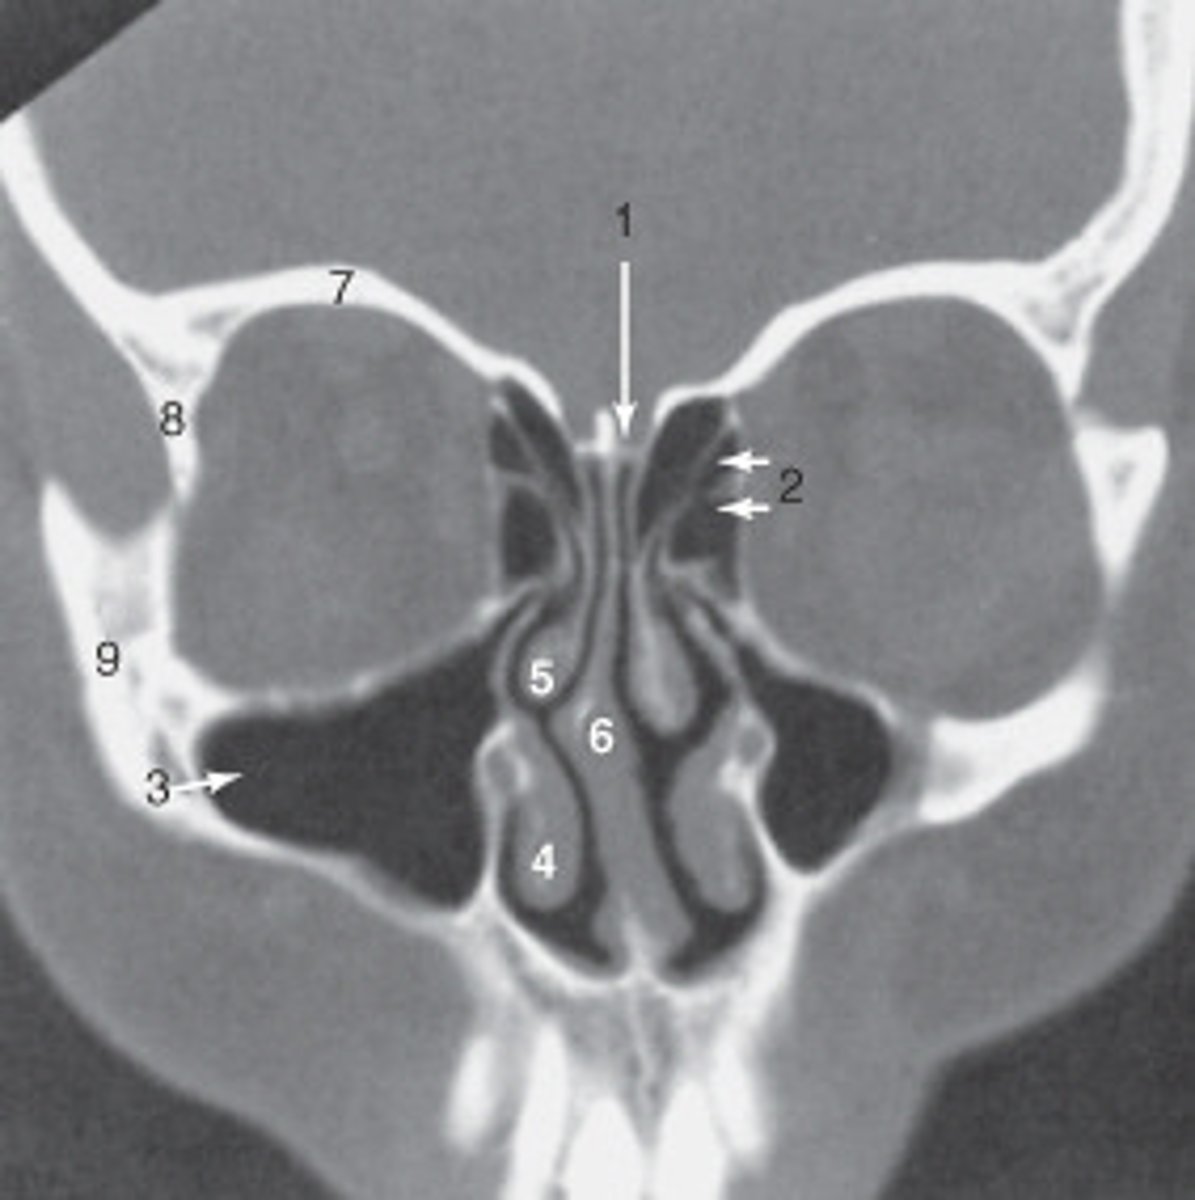

the nasal septum is labeled:

<p>the nasal septum is labeled:</p>

the ethmoid sinuses are labeled:

<p>the ethmoid sinuses are labeled:</p>

the zygoma is labeled:

<p>the zygoma is labeled:</p>

the lateral orbital wall is labeled:

<p>the lateral orbital wall is labeled:</p>

the structure labeled 3 is the:

<p>the structure labeled 3 is the:</p>

the structure labeled 7 is the:

<p>the structure labeled 7 is the:</p>

The sphenoid sinus is labeled:

<p>The sphenoid sinus is labeled:</p>